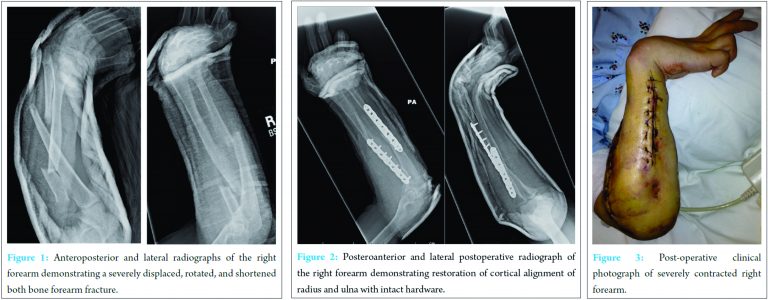

A 39‑year‑old female presented as an unrestrained driver involved in a high‑velocity motor vehicle accident. After initial stabilization, secondary survey demonstrated an acute, osseous deformity of the right forearm with a concomitant Volkmann’s contracture. Neurovascular examination was intact but limited secondary to the chronic contracture. The radiographic examination revealed a displaced and shortened BB forearm fracture (Fig. 1). Past medical history revealed longstanding substance abuse with a previous right forearm compartment syndrome. 6 years prior, she was found unconscious for an unknown duration on her right arm while in a drug‑induced haze. Despite emergent dorsal and volar fasciotomy, extensive myonecrosis was observed intraoperatively and she, subsequently, developed a Volkmann loped a Volkman. Clinical examination of the contracture demonstrated a static wrist flexion contracture of 90° with clawing deformities of the small and ring fingers lacking any functional pronation or supination. The thumb was held in a fixed flexion deformity, while the index and long fingers exhibited a 35° extension contracture at the metacarpal phalangeal joints with limited motion at the distal interphalangeal and proximal interphalangeal joints. Her elbow range of motion was limited to a 35° arc of motion (75‑110°). Despite these deformities, the patient reported her right upper extremity was integral in her activities of daily living. She has been able to drive an automatic transmission vehicle using her left upper extremity without difficulty despite her contracture on the right.

Operative intervention with ORIF and compression plating was performed. The ulna was exposed through the flexor carpi ulnaris and extensor carpi ulnaris interval. A dorsal approach between extensor carpi radialis brevis and extensor digitorum comminus was utilized as previous skin grafting and fasciotomy scarring precluded the use of a volar incision (Fig. 2). Despite a general anesthesia, paralytics and a supraclavicular block, intraoperative restoration of forearm length was impossible due to the forearm contracture. Ulnar and radial osteotomies of 2.1 cm were required to achieve reduction of the forearm with two 7‑hole limited contact dynamic compression plates (Fig. 2). The osteotomy of 2.1 cm was the minimal amount of bone resection possible that would allow us to realign the fracture. No soft tissue, release was performed given her longstanding contractures and to minimize compromise of soft tissues for fracture site healing. Post‑operative evaluation demonstrated no complications, well‑healed incisions, intact hardware, and a maintained forearm reduction (Fig. 3). At final follow‑up of 4 months, her range of motion of the elbow and wrist were unchanged from her preoperative examination (75‑110° elbow motion and a fixed 90° wrist flexion contracture), and she fully regained her preoperative functional ability.